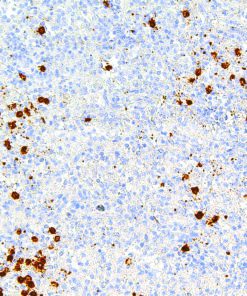

Thymidylate Synthase

Thymidylate Synthase (TS) is a crucial enzyme responsible for the synthesis of 2′-deoxythymidine-5′-monophosphate (dTMP) a precursor for thymidylate which is necessary for DNA replication and repair from 2′-deoxyuridine-5′-monophosphate (dUMP). In terms of cancer, TS is an important target for cancer treatment as the inhibition of TS and therefore nucleotide synthesis necessary for cell growth has shown to be a vital part for successful treatment against colorectal, pancreatic and breast cancers.

| Clone | IHC697 |

| Source | Mouse Monoclonal |

| Positive Control | Colon Cancer |

| Dilution Range | 1:100 – 1:400 |